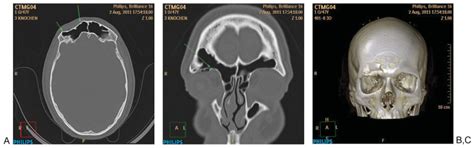

The Comprehensive AOCMF Classification System: Radiological Issues and ...